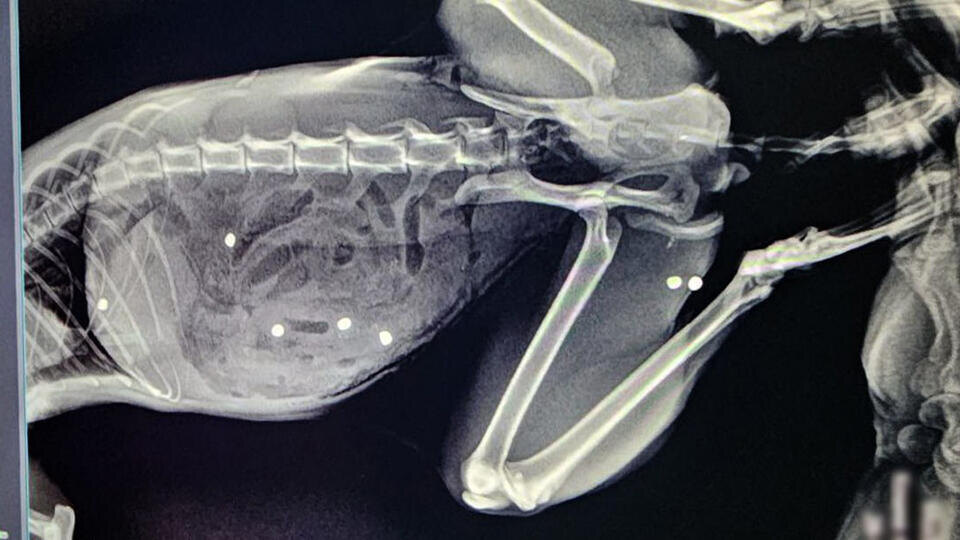

Кота более чем с 20 пулевыми ранениями спасли в ветклинике в Зеленограде. Об этом 28 ноября сообщили в телеграм-канале сети государственных ветклиник Москвы ГБУ "Мосветобъединение". "В Зеленоградской ветклинике спасли кота с множественными пулевыми ранениями. Питомец, по словам владельцев, пострадал во время прогулки в частном секторе", – говорится в сообщении. У пятилетнего кота по кличке Тимофей был пробит кишечник в 24-х местах и в двух местах селезенка, также пули попали в грудную клетку и мышцы бедра. В ветклинике отметили, что хирург немедленно приступил к операции, на которую потребовалось более трех часов. Почти безнадежный, как отметили в клинике, пациент был спасен. "Под конец операции и кот, и я выглядели одинаково. Не скрою, горжусь собой на 100%, но еще больше котом! Несмотря нa все усилия живодеров, котик жив!" – сообщил ветврач. Раны кота Тимофея полностью зажили, его здоровье вне опасности, заключили в ветклинике. 22 ноября сообщалось, что кот по имени Аса был возвращен

У пятилетнего кота по кличке Тимофей был пробит кишечник в 24-х местах и в двух местах селезенка, также пули попали в грудную клетку и мышцы бедра.